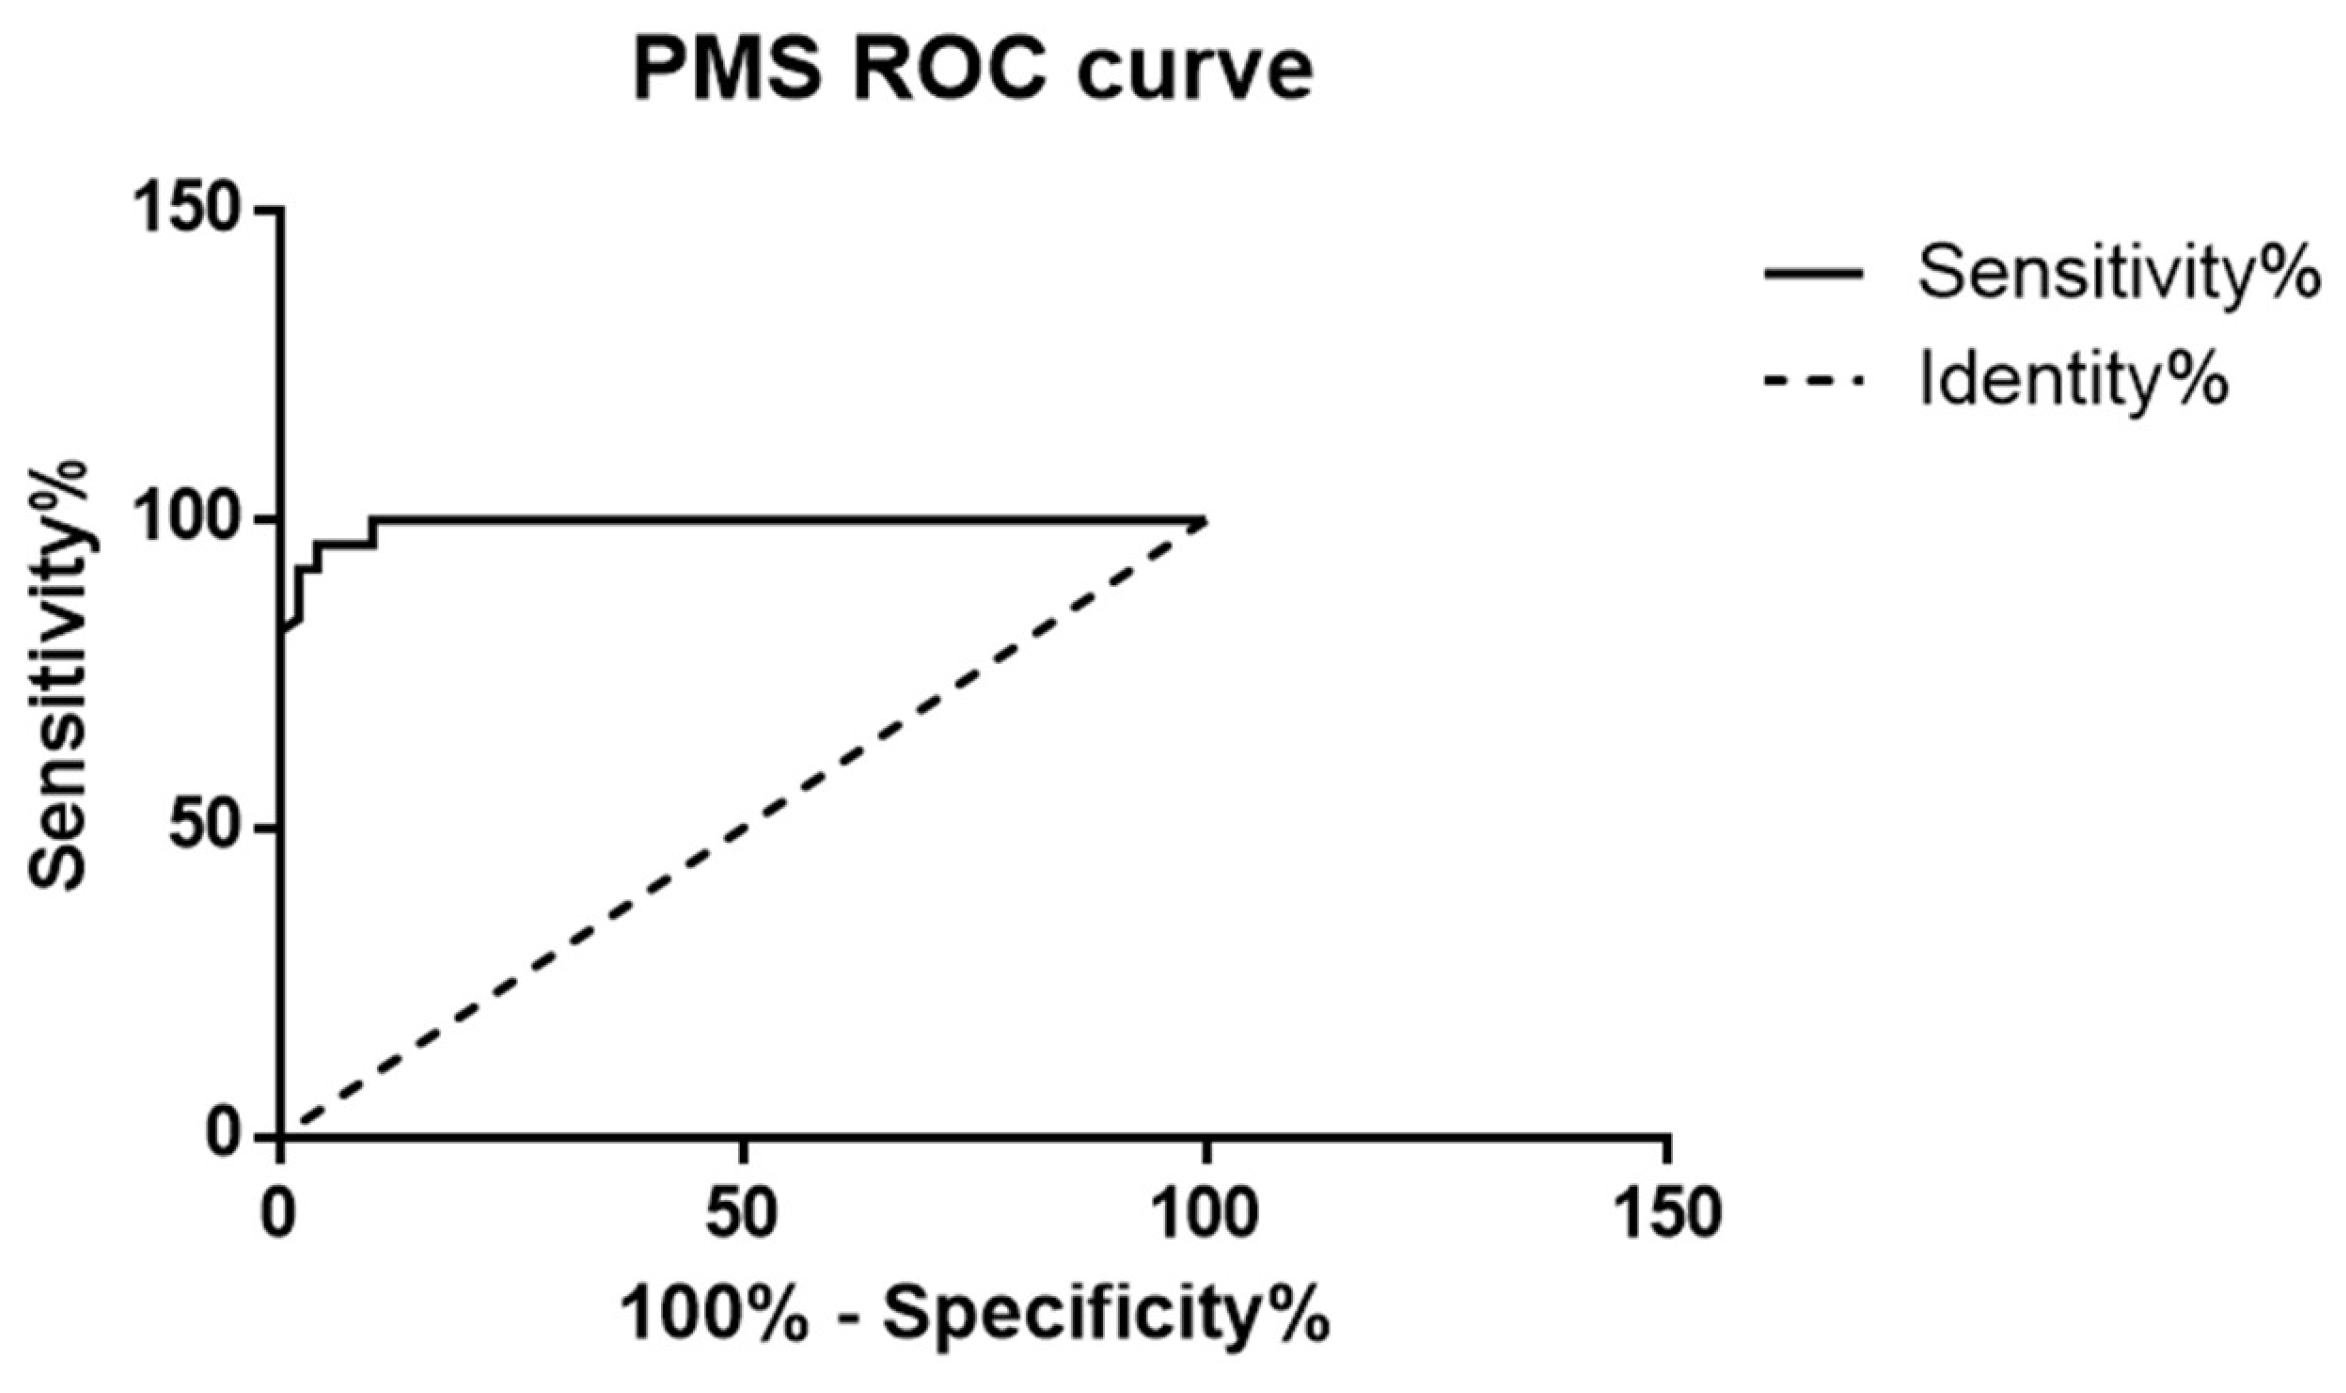

3. Results